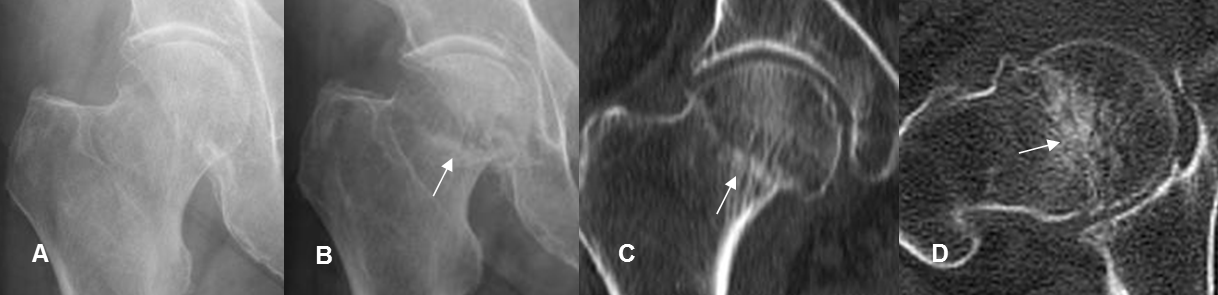

Fig 70 A. Fractura de stress.

A: Rx lateral. Paciente con antecedente de trauma, sin encontrar fracturas.

B: Rx lateral. Una semana después y con persistencia del dolor. Se encuentra imagen densa y en sentido transverso, a nivel subcapital, que corresponde a la formación de callo óseo.

C: TAC reconstrucción coronal y D: TAC axial.